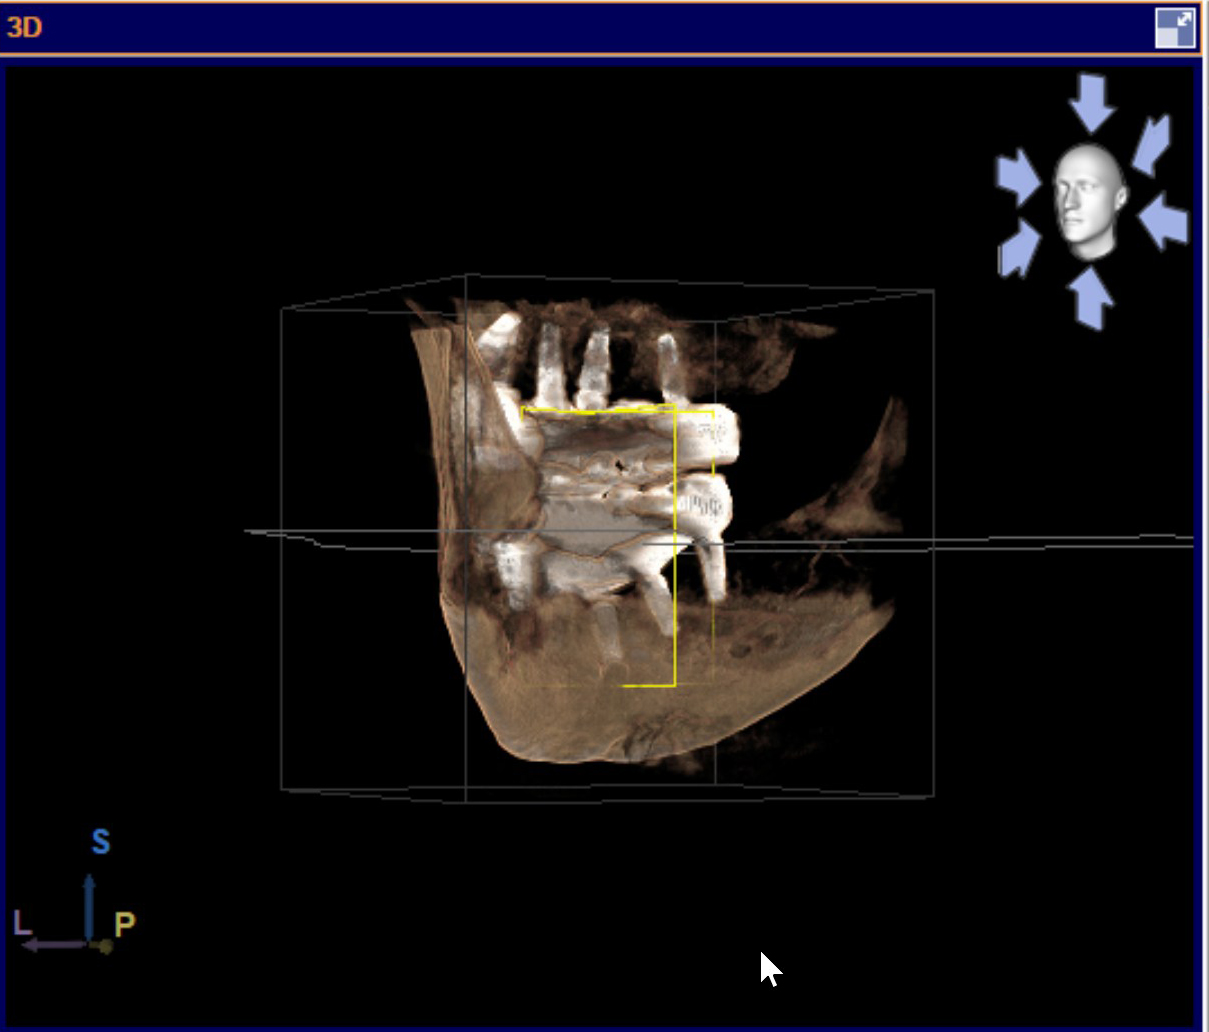

There are several issues with all of the implants, from problems with their locations, problems with mismatched heights from one implant to another, problems with their depth requiring gum grafts as there is no attached gingiva, problems with two of the upper implants apparently touching each other per periodontist report, a few other issues, and all seem to have some level of bone loss around the implants.

All the problems with the implants are creating all sorts of uneven pressures on the implants and my jaws. Implants were carelessly placed haphazardly, then Bansal bragged about how he had never completed a full mouth surgery in such a short amount of time as it took to do my mouth.

Dental experts opinioned that the All on X that was done to me by Dr Shobhit Bansal is a dismal and unprofessional failure. It's like everything that could be wrong is wrong.

According to the dental experts I consulted, the haphazard placement of the implants that Bansal did creates all sorts of uneven pressures on the implants, the prosthesis, and my jaws. That explains the problems with the temporary prosthesis breaking at the screws, as well as the screws loosening and unusual bone loss at the implants.